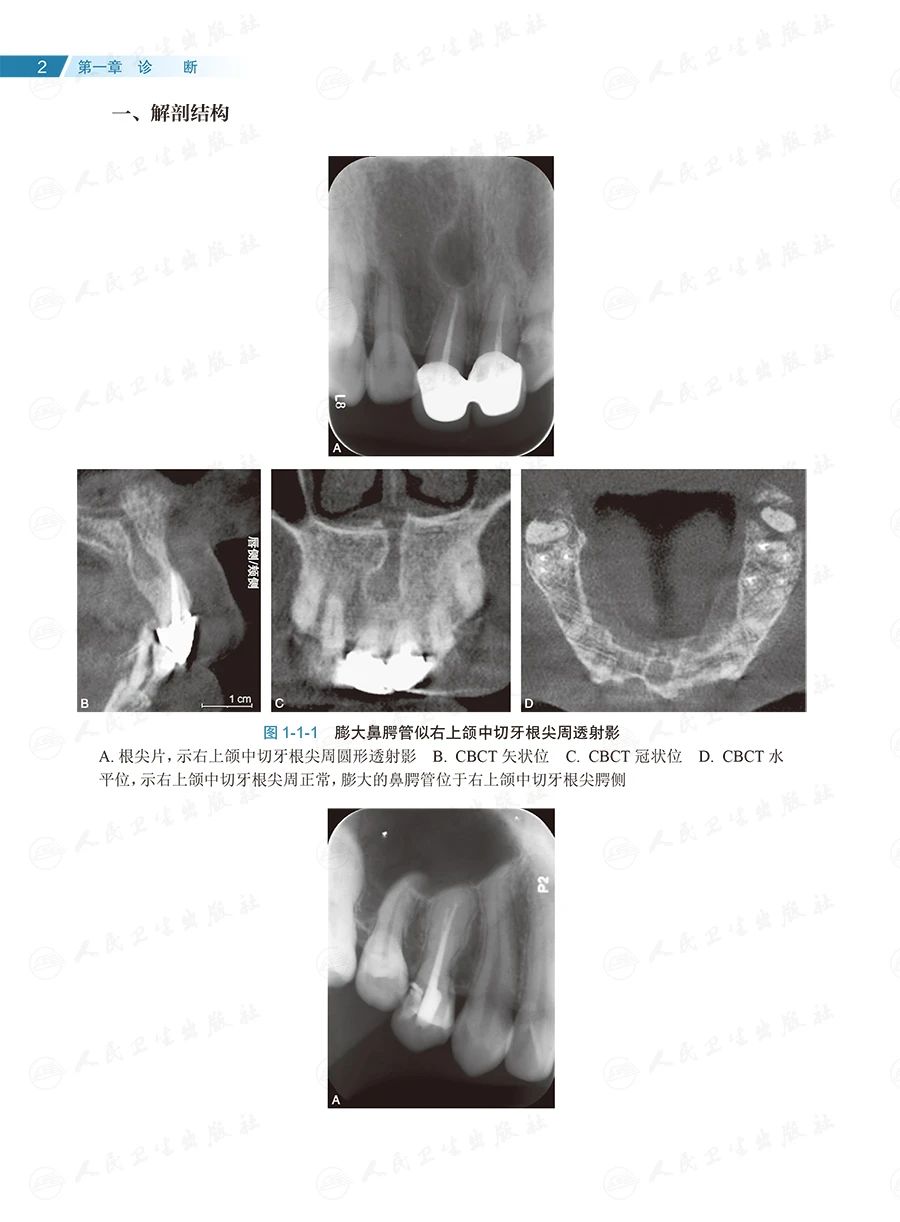

全书共133个临床病例、约1400幅照片,内容全面、图文并茂、形象直观。按照诊断、确定治疗方案和治疗的顺序,全书分为六章:第一章为诊断,主要讨论根尖周透射影、根裂的诊断和鉴别诊断;第二章为治疗方案选择,重点探讨非手术和手术(再)治疗方案的选择;第三章为在体手术治疗,即显微根尖外科,讨论特定牙位和牙根的手术,以及一些复杂疑难牙髓病、根尖周病的手术治疗;第四章为离体手术治疗,即显微意向再植术,全面讨论其适应证;第五章为多学科合作,包括牙髓源性上颌窦炎、联合应用引导性组织再生术(guided tissue regeneration,GTR)、自体牙移植术中的应用;第六章为全文总结,系统阐明牙髓病、根尖周病治疗的整体策略。